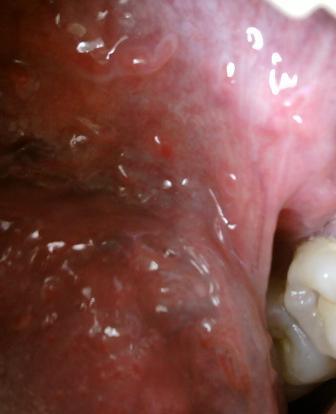

石家庄九州皮肤病医院 > 尖锐湿疣 > > > 治疗尖锐湿疣医院哪家费用低专家温馨提示:对于尖锐湿疣这种顽固性疾病,早发现早治疗对于疾病的治疗和康复是很关键的。因为任何疾病在早期都是治疗疾病的关键时期,此外关于尖锐是有点治疗方法以及治疗费用也是大家比较关心的一个问题。

治疗尖锐湿疣医院哪家费用低在此石家庄九州皮肤病医院专家温馨提示:关于尖锐湿疣的治疗费用其实并没有想象中的那么高,一般在几百元左右的样子,但是不同患者具体病情不同,选择 不同治疗方法,治疗时间的差异等等,都会影响尖锐湿疣的治疗费用。但是关于尖锐湿疣的治疗,大家也不要贪图便宜,而去一些小诊所治疗,这是因为小的诊所,一般医疗条件都是有限的,是不可能从根本上治愈尖锐湿疣的。现在尖锐湿疣的发病率是很高的 ,因此建议大家在平时应该引起注意。